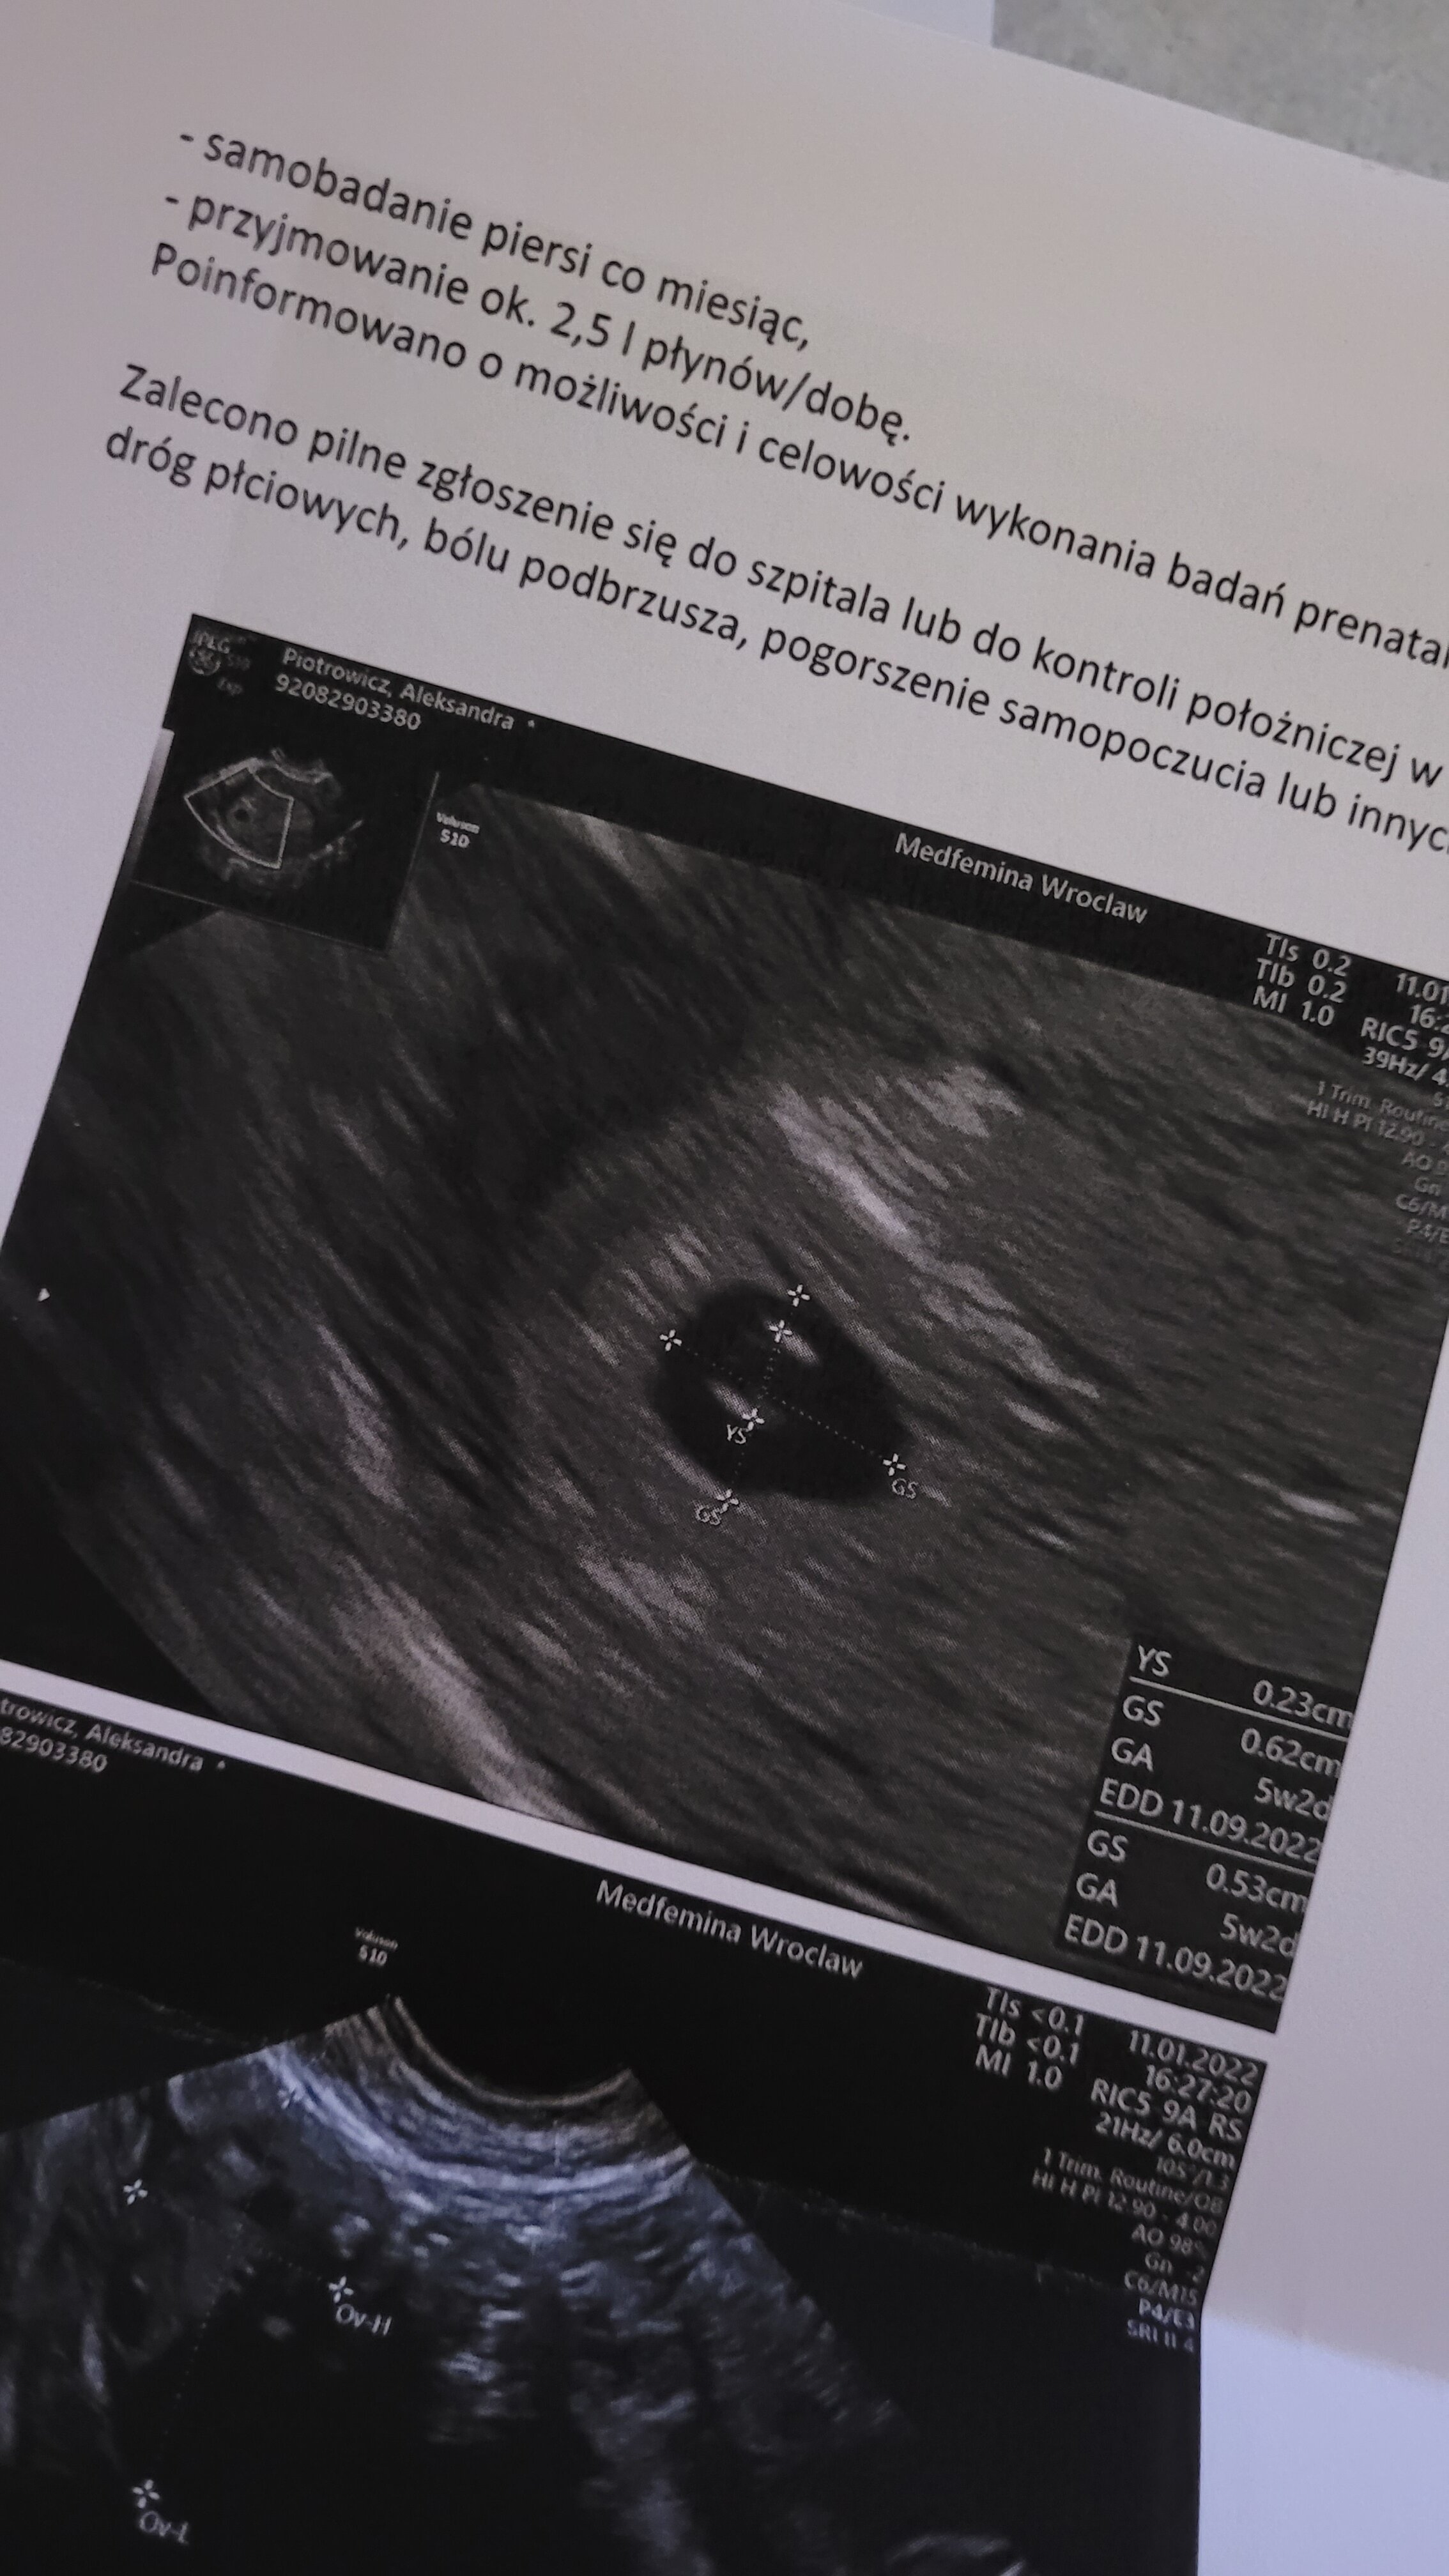

W końcu stwierdziłam że tutaj napisze mimo że nie mam jeszcze poczucia bycia w ciazy bo stwierdzam że w tak wczesnej ciazy nic nie jest pewne :) staraliśmy się z partnerem o dzidziusia z 1,5 roku, miałam podejrzenie cykli bezowulacyjnych, po czym się poddałam i mając z tyłu głowy że może nigdy nie będzie nam to pisane żyłam z dnia na dzień. No i stała się niespodzianka! Niestety z racji tego że moje cykle są strasznie nieregularne nie mialam możliwości wyliczania czegokolwiek jednak 4.01 zrobiłam test i wyszedl pozytywny. Tego samego dnia zrobiłam betę i wyszla 793 po dwóch dniach prawie 2200. Umówiłam się do ginekologa 5 dni później który po wielkości pęcherzyka płodowego i obecności pęcherzyka żółtkowego stwierdził 5 tydz I 2 dzień. Dzisiaj wypada już że to 6 tydz I 1 dzień. Termin porodu wstępnie ustalony na 11.09. Dalej się boję i nie chce nikomu mówić. Kolejne badanie mam 27.01. Chciałabym już pójść ale stwierdzam że skoro moja doktor nie kazała mi przychodzić wcześniej dobrze wie co robi i że na ten moment wszystko wygląda dobrze. Planowałam o ciazy powiedzieć w dzień babci i dziadka ale stwierdziłam że chce poczekać do kolejnego badania. Mam nadzieję że wszystkie dobrze zniesiemy ciążę i będziemy się wspierać w tym pięknym ale jakże stresującym okresie!

A no i tak ostatnio wyglądał obraz na usg 😀